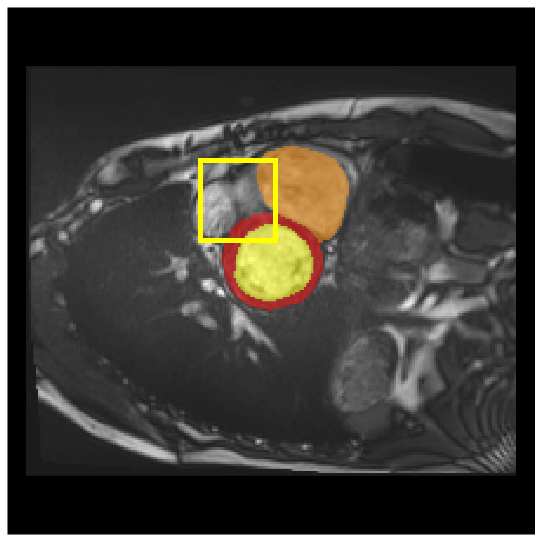

Medical image segmentation plays a critical role in various diagnostic workflows, as it enables accurate delineation of anatomical structures and pathological regions, thereby enhancing disease interpretation, treatment planning, and outcome prediction. Jang et al. [1] has demonstrated that improved segmentation performance can lead directly to reduced diagnostic error rates and increased clinician confidence. Building on the remarkable success of deep learning across diverse domains [2, 3, 4, 5], recent progress in medical image segmentation has been primarily driven by deep learning. Since the introduction of U-Net [6], segmentation methods have rapidly evolved, with convolutional neural networks (CNN)-based models [7, 8, 9] and Transformer-based models [10, 11, 12] showing superior performance in computed tomography (CT) and magnetic resonance imaging (MRI) segmentation. However, various challenges such as blurriness, noise, and low contrast often hinder the accurate diagnosis of diseases. Applying various image enhancement techniques to generate an enhanced image from the input can alleviate this problem, as existing methods have demonstrated improved segmentation accuracy [13, 14, 15]. Nevertheless, input images may unintentionally lose crucial information contained in the original image during enhancement. As a result, the segmentation model suffers from performance degradation (Fig. 1(a) and (b)). Therefore, we argue that it is crucial to leverage the advantages of both the original and enhanced images through image fusion strategies.

4.3.2 Visual Comparisons

Visualization of our method on the Synapse and ACDC datasets is shown in Fig. 3(a) and Fig. 3(b). For the Synapse dataset illustrated in Fig. 3(a), FCT failed to accurately segment SM and GB, while MERIT achieved precise segmentation of SM but struggled with GB. In contrast, our method achieved accurate segmentation of both SM and GB. Regarding the ACDC dataset shown in Fig. 3(b), while previous methods achieve comparable segmentation of the Myo and LV to the GT, they exhibit noticeable errors on the RV, including invasion into adjacent organs and misrecognition. On the other hand, our method accurately segments across all three structures Myo, LV, and RV, performing as precisely as the GT. We demonstrate the superiority of our method quantitatively and qualitatively.